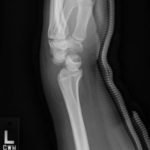

Perilunate Dislocation

A 25-year-old female presented to the emergency department with left wrist pain following a fall off a skateboard. The patient fell on her outstretched left wrist with the wrist dorsiflexed and reported immediate sharp pain to her left wrist that was worse with movement. She denied other trauma.

In the left lateral wrist x-ray, the lunate (outlined in blue) is dislocated from the rest of the wrist bones (yellow line) but still articulates with the radius (red line). The capitate (yellow line) does not sit within the distal articulation of the lunate and is displaced dorsally. Additionally, a line drawn through the radius and lunate (green line) fails to intersect with the capitate. This is consistent with a perilunate dislocation. This is compared to a lunate dislocation, where the lunate itself is displaced and turned ventrally (spilled teacup) and the proximal aspect does not articulate with the radius.

A perilunate dislocation is a significant closed wrist injury that is easily missed on standard anterior-posterior imaging. These dislocations are relatively rare, involving only 7% of all carpal injuries and are associated with high-energy trauma onto a hyperextended wrist, such as falls from a height, motor vehicle accidents, and sports injuries.1 An untreated perilunate dislocation is associated with high risk of chronic carpal instability and post-traumatic arthritis. If the mechanism of injury is sufficient to suspect perilunate dislocation, multiple radiographic views of the wrist should be ordered. Patients should receive prompt orthopedic consultation for open reduction and ligamentous repair. Even after successful identification and subsequent surgical repair, median nerve neuropathy and post-traumatic arthritis are frequent.2-3